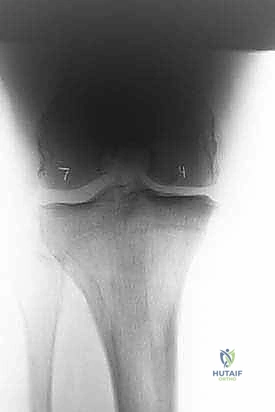

تُعد الأشعة السينية (X-rays) الممتدة من الحوض إلى الكاحل (Scanogram) ضرورية جداً لحساب زاوية التقوس بدقة وتحديد مقدار التعديل المطلوب جراحياً.

قبل العملية، يتم قياس زوايا الركبة بدقة متناهية. كل درجة من درجات التعديل يتم حسابها مسبقاً.